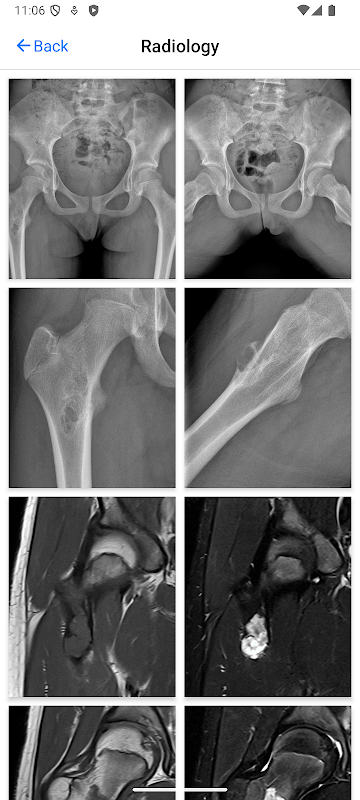

BoSTT يجلب للمستخدم تجربة حقيقية من الحالات المتكررة والنادرة، نموذجية وأكثر غرابة من العظام والأورام الأنسجة اللينة. كل حالة لها تاريخ السريري، وارتفاع القرار الأشعة وعلم الأمراض الصور والتشخيص والعلاج ونقاط التعلم.